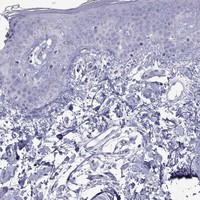

Enhanced - Orthogonal

Antibody staining mainly consistent with RNA expression data across 43 tissues.

Skin 1

RNA expression: 0.0 nTPM

HIER pH6

Antibody dilution 1:600